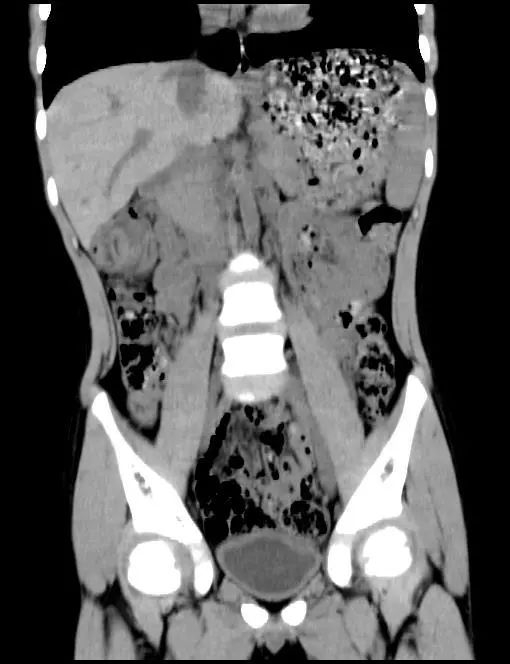

腹部CT出来后,提示结肠肝区似同心圆样改变,难道是肠套叠吗?

我立即嘱患儿完善腹部B超,结果也提示肠套叠!那这万万不可马虎,又立即予空气灌肠,但空气灌肠后未见明显肠套叠,升结肠却发现了类圆形块影……这是怎么回事?